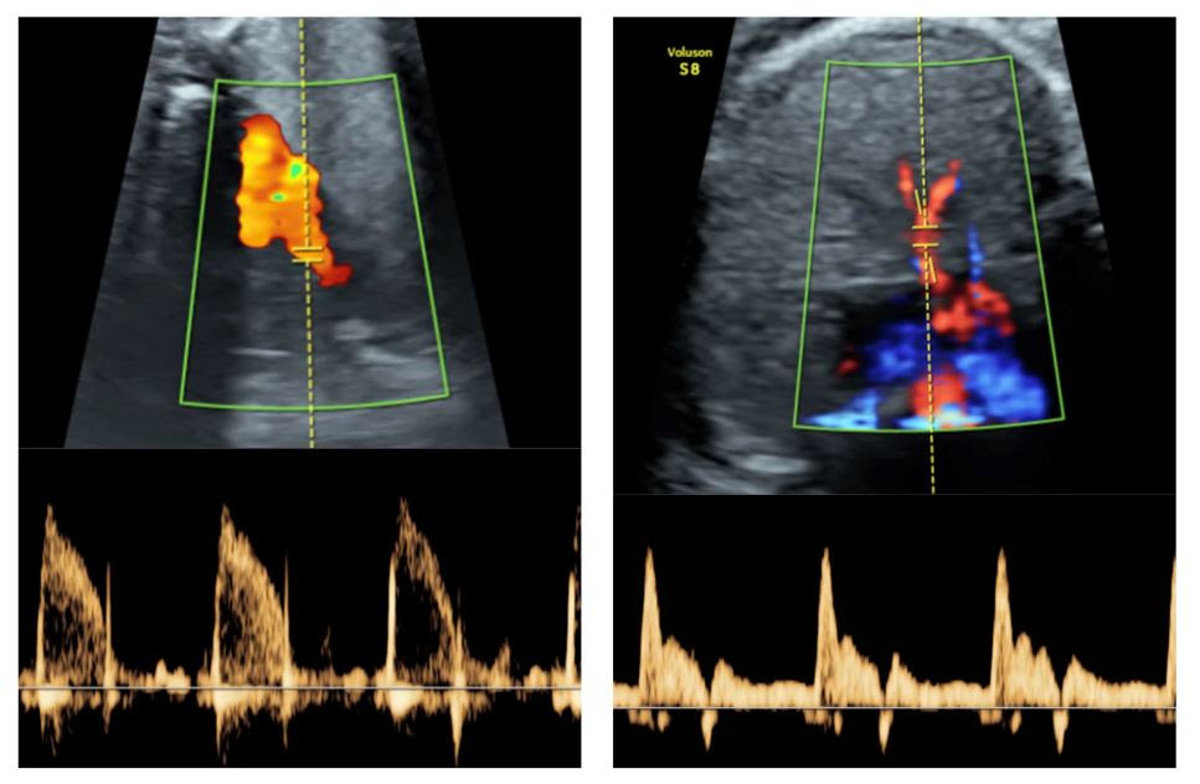

Reactividad vascular de pulmones de fetos demasiado pequeños (a la izquierda, las principales arterias pulmonares; a la derecha, imatge de les arterias intrapulmonares)

Reactividad vascular de pulmones de fetos demasiado pequeños (a la izquierda, las principales arterias pulmonares; a la derecha, imatge de les arterias intrapulmonares) - UNIVERSITAT POMPEU FABRA